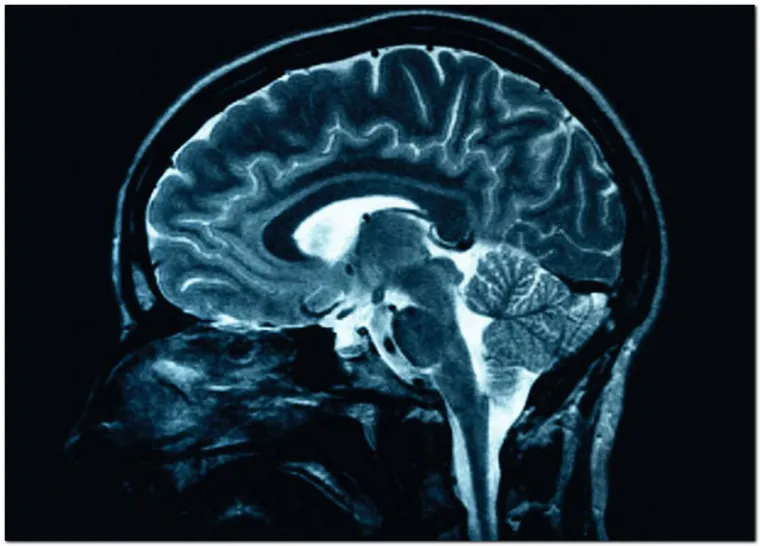

Marihuana je lijek, ali i mogući uzrok bolesti: evo gdje pomaže, a gdje odmaže

O marihuani kao lijeku i dalje se lome koplja, iako ljudi već 3000 godina liječe bolesti ovom biljkom. U posljednje vrijeme sve više zemalja legalizira marihuanu u zdravstevne svrhe, no i dalje nema dovoljno dokaza koje joj idu u prilog. Evo koje su medicinske dobrobiti marihuane, a kod čega ne pomaže ili čak radi i veliku štetu za zdravlje